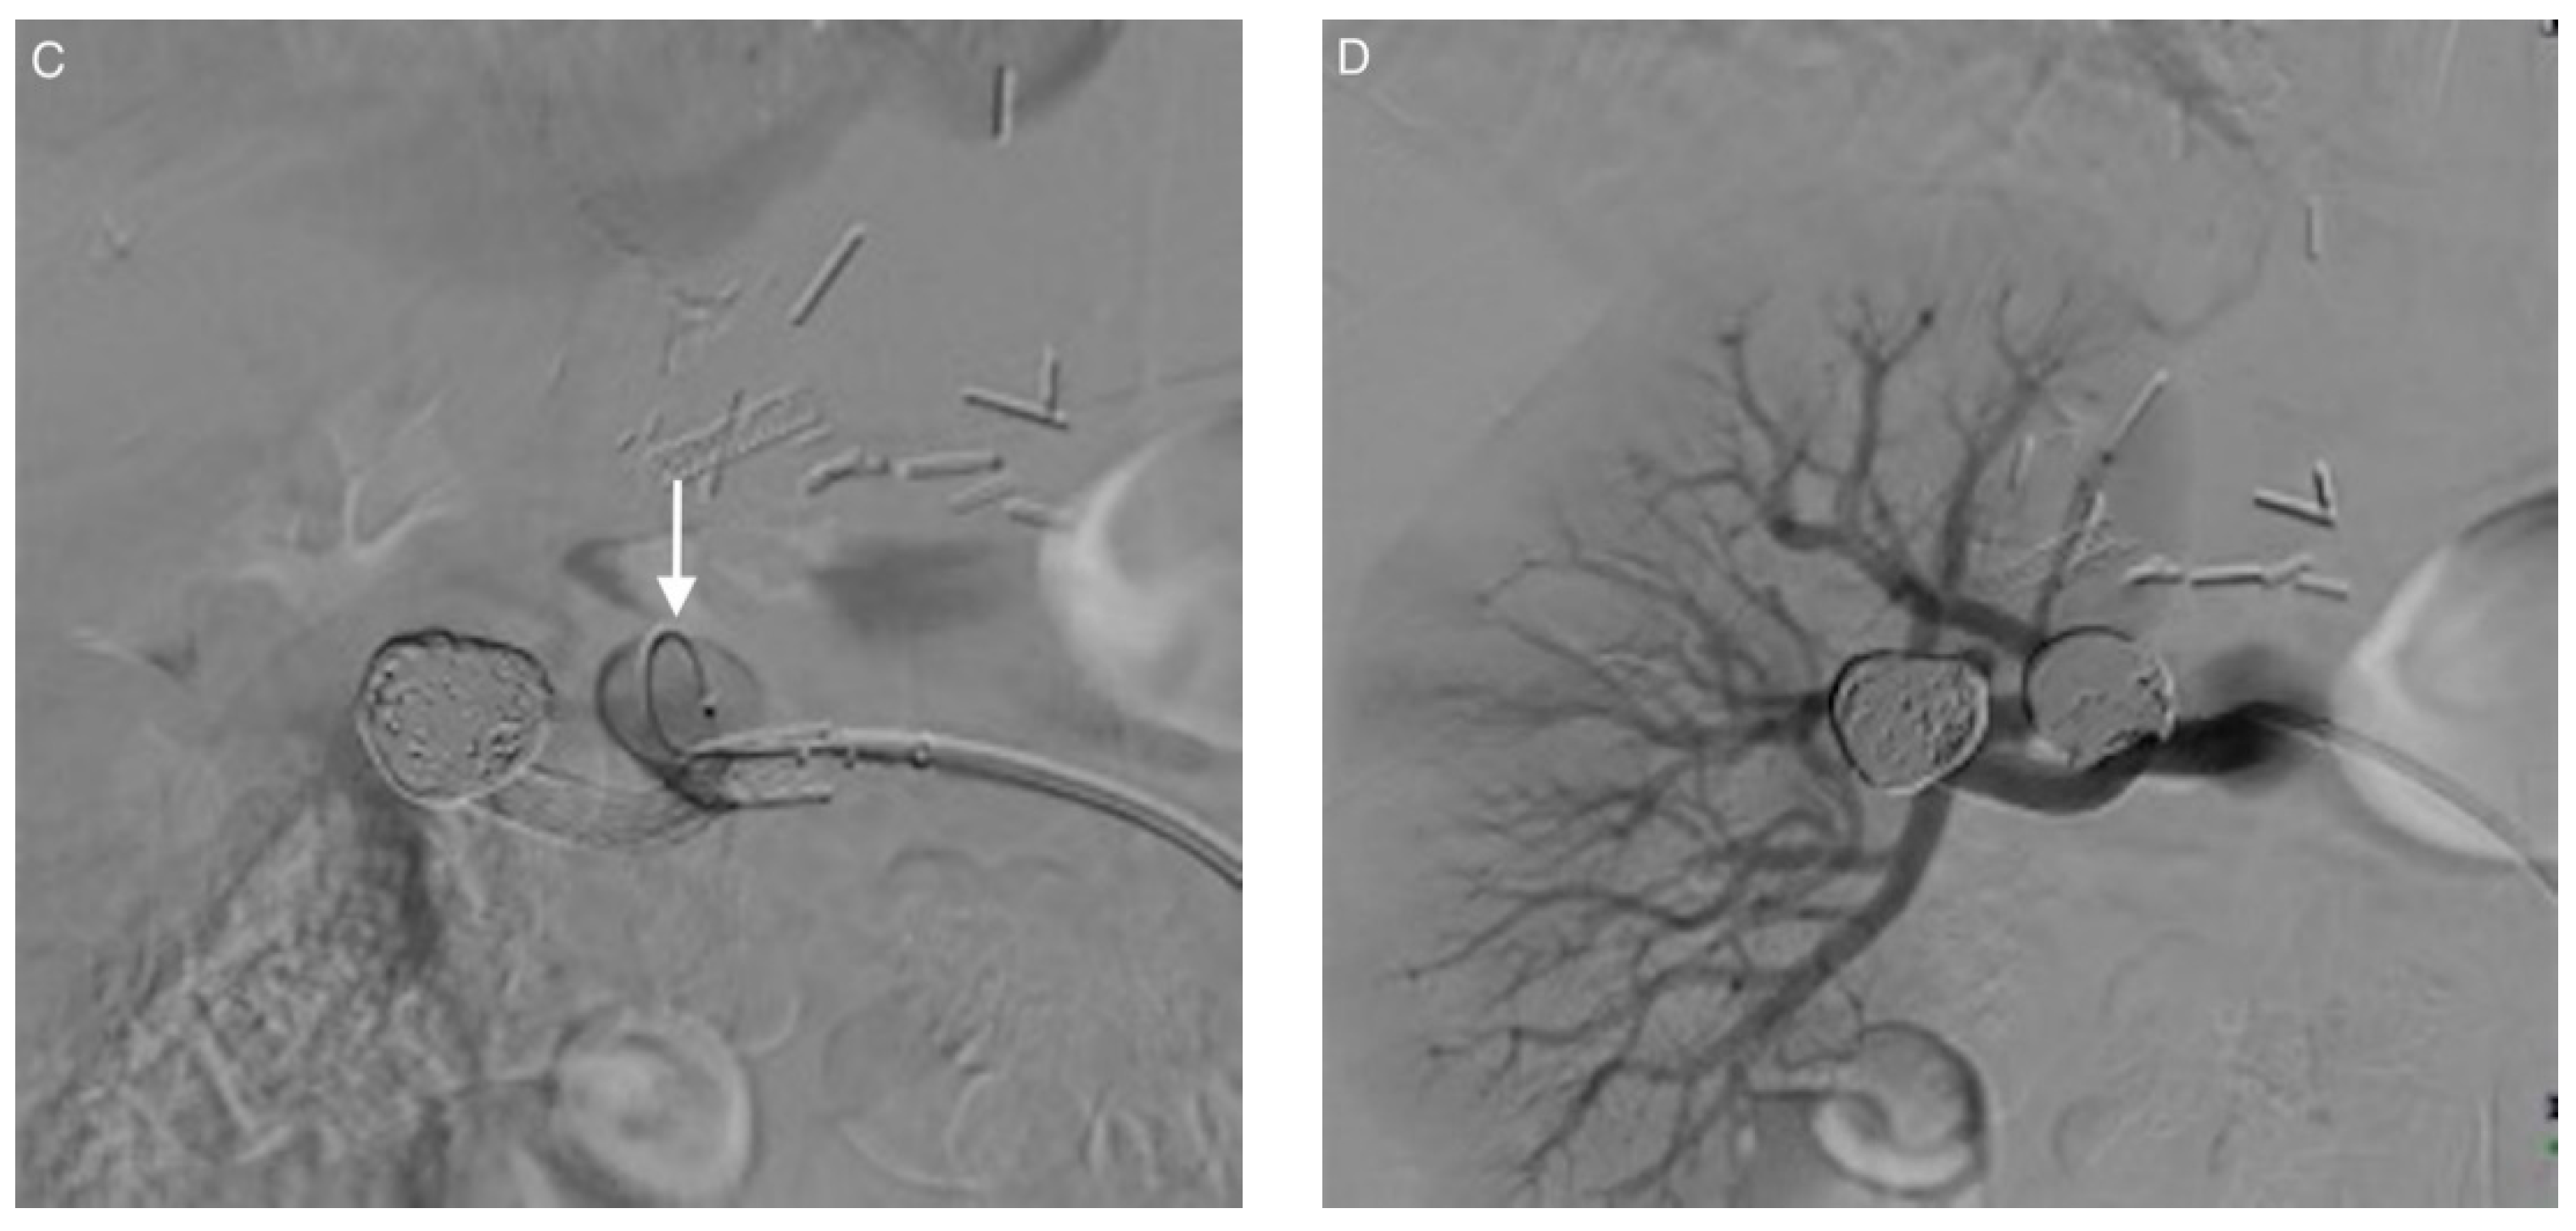

3.3. Coil Embolization and Outcomes